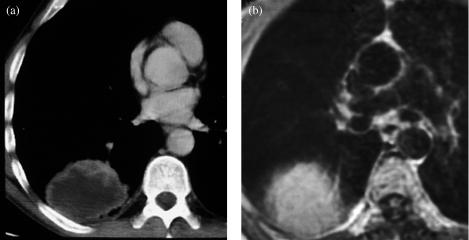

Effective treatment for carcinoma of the lung remains one of the biggest challenges in oncology. Radical radiotherapy may be a curative option for patients who are unsuitable for radical surgery either because of disease stage or because of co-morbidity. Long-term disease control with radical radiotherapy is disappointing with only about 6% of patients treated being alive at 5 years. Technological advances involved in the planning and delivery of radiotherapy may improve this. The advent of conformal radiotherapy, utilizing computed tomography and three-dimensional planning systems, allows much more accurate shaping of the radiation fields. This greater accuracy of target volume definition facilitates a reduction in the radiation dose to normal tissues, allowing for dose escalation to the tumour. Delineation of the target volume can be problematic. Conventional CT has limitations in term of distinguishing between benign and malignant tissues, e.g. the size criteria for involved lymph nodes. The oncologist uses a combination of radiological and clinical information when defining the target volume but their radiological interpretation of imaging is inferior to that of a radiologist. The Royal College of Radiologists (RCR) issued guidance in 2004 on the optimal imaging strategies for common cancers. These guidelines address issues regarding the localisation and staging of cancers and treatment planning, and also reporting and training. They recommend the development of closer links between radiologists and oncologists to optimise the interpretation of imaging and target volume definition. This article aims to briefly explain the planning process involved in irradiating lung cancers, highlight problematic areas and suggest ways in which co-operation with radiologists may improve the delivery of radiotherapy and therefore the treatment outcomes for this group of patients.

肺癌的有效治疗仍然是肿瘤学领域最大的挑战之一。对于因疾病分期或合并症而不适于根治性手术的患者,根治性放疗可能是一种治愈性选择。根治性放疗的长期疾病控制效果令人失望,接受治疗的患者中只有约6%能存活5年。放疗计划和实施过程中的技术进步可能会改善这一情况。适形放疗的出现,利用计算机断层扫描和三维计划系统,能够更精确地塑造辐射野。靶区定义的更高准确性有助于减少对正常组织的辐射剂量,从而可以提高肿瘤的照射剂量。靶区的勾画可能存在问题。传统CT在区分良性和恶性组织方面存在局限性,例如受累淋巴结的大小标准。肿瘤学家在定义靶区时会综合运用放射学和临床信息,但他们对影像的放射学解读不如放射科医生。英国皇家放射科医师学院(RCR)在2004年发布了关于常见癌症最佳影像策略的指南。这些指南涉及癌症的定位、分期和治疗计划等问题,以及报告和培训。它们建议放射科医生和肿瘤学家建立更紧密的联系,以优化影像解读和靶区定义。本文旨在简要解释肺癌放疗的计划过程,突出存在问题的领域,并提出与放射科医生合作可能改善放疗实施从而提高这类患者治疗效果的方法。